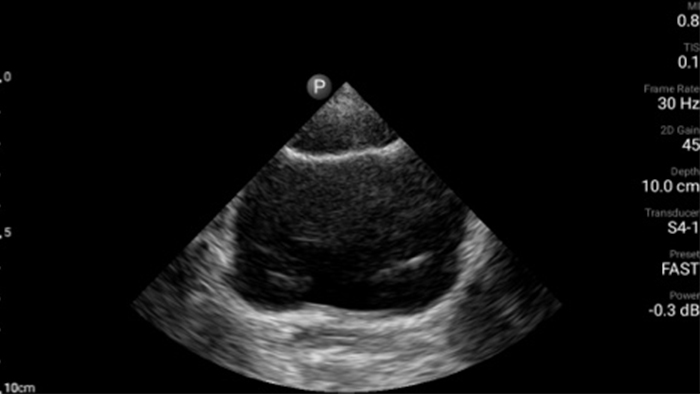

Emergency medicine

“Lumify has excellent image quality and is easy to use.”

Dr. Darren Braude, Emergency Medicine